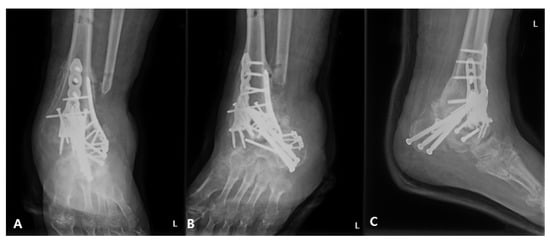

2.2. Surgical Procedure

2.3. Postoperative Care